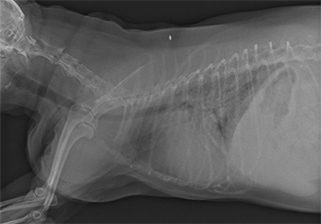

- 胸部X線検査にて、心陰影の拡大および左肺後葉領域の不透過性亢進像が認められた。

明らかな腹水貯留は認められなかった。 - 心エコー図検査にて、僧帽弁の逸脱とそれに伴う僧帽弁逆流が認められた。